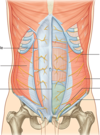

Label this image

Label this image